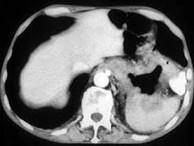

问题 男,57岁,腹部隐痛不适伴低热2月余,腋下可触及数个肿大的淋巴结,请结合图像,作出诊断()

选项 A.左侧肾上腺癌并胃脾转移 B.左侧恶性嗜铬细胞瘤侵及胃脾 C.左侧肾上腺淋巴瘤且胃脾受累 D.左侧肾上腺腺瘤 E.左侧肾上腺转移瘤

答案 C